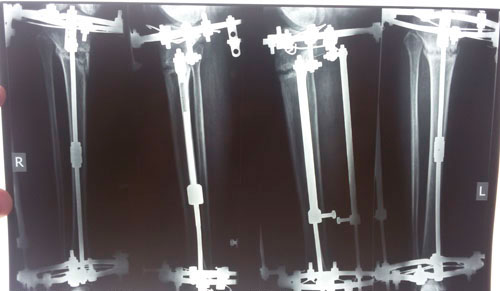

Исходник.

РЕНТГЕН ДО ОПЕРАЦИИ